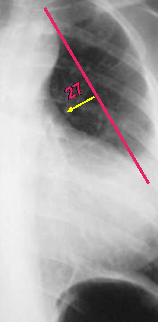

Main pulmonary

artery is more

than 15 mm

from tangent

Small pulmonary

artery

Truncus arteriosus

Tetralogy of Fallot